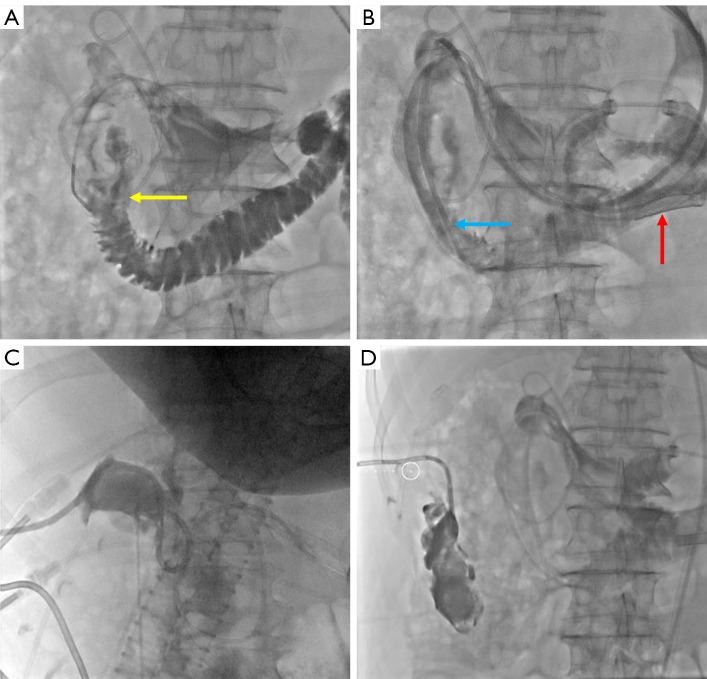

Case description: This retrospective study reviewed seven cases showing duodenal perforation after ERCP for choledocholithiasis between 2019 and 2024. The patients showed clinical symptoms such as fever, abdominal pain, and abdominal distension within 1-3 days after ERCP, and were managed with the interventional three-tube method (insertion of a nasointestinal feeding tube for enteral nutrition, a gastrointestinal decompression tube, and a percutaneous drainage tube for drainage of pus and air). After 5-7 days of hospitalization, the patients were discharged upon stabilization. All patients showed successful healing of duodenal perforation during follow-up.